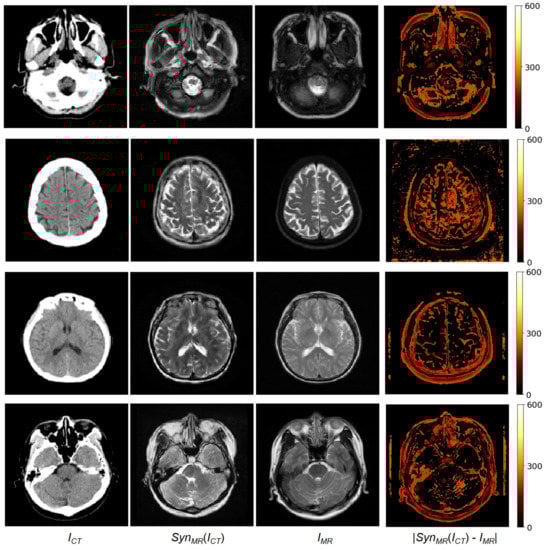

Our dataset includes unpaired data of 182 patients and paired data of 20 patients. To train MR-GAN with paired and unpaired data, all the unpaired data were used as training data, and the 20 paired data were equally separated into two groups: 10 pairs for the training set, and the other 10 pairs for the test set. Moreover, one patient’s paired data volume includes about 35 2D axial image slices of CT and MR. There were a total of 366 2D axial image slices in the test set. The same training and test set were used for all the experiments: First, the synthesized MR images were compared with the reference MR images that had been carefully registered to become paired data with CT images. For brevity, the method developed in this study is referred to as the MR-GAN. Figure 5 shows four examples of an input CT image, a synthesized MR image obtained using MR-GAN, a reference MR image, and the absolute difference maps between the synthesized and reference MR images. It is worth mentioning that we reduced the original difference range to 0 , 600 to make the absolute difference much clearer for the analysis. The MR-GAN learned to differentiate between different anatomical structures with similar pixel intensity in CT images (such as bones, gyri, and soft brain tissues). The largest differences were found in the area of bony structures, while the smallest differences were found in the soft brain tissues. This may be partly due to the misalignment between the CT and the reference MR images and because the CT image provides more detail about the bony structures to complement the shortcoming of the synthesized MR, which is focused on the soft brain tissues.

Figure 5. From (left) to (right): Input CT, synthesized MR, reference MR, and absolute error between reference and synthesized MR images.